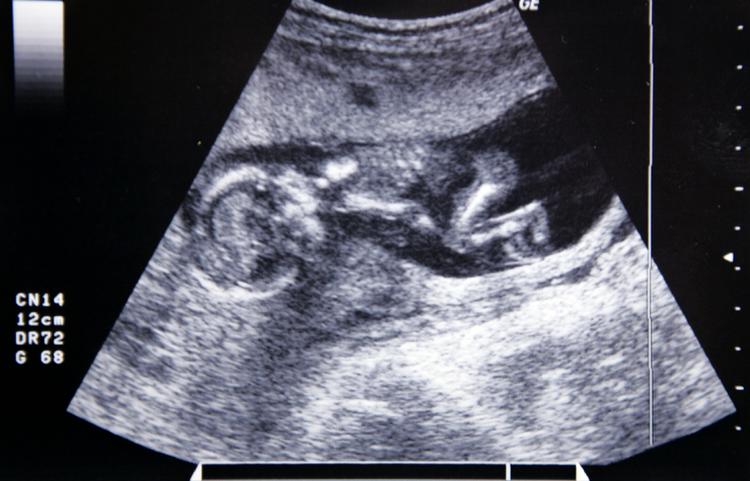

Overlæge: Tilbyd alle, der ønsker sen abort, en dødssprøjte til fostret

optælling. Landets største fødested, Skejby Sygehus i Aarhus, har som det første sted talt op, hvor mange sent aborterede fostre, der var i live. Svaret var hver sjette.

Alle gravide, der skal have udført en sen abort, bør orienteres om muligheden for at få en kaliumsprøjte. Den vil sikre, at fostret dør, inden det bliver født, siger overlæge Kresten Rubeck Petersen, der er formand for Dansk Selskab for Obstetrik og Gynækologi.

»En sen abort er meget belastende for kvinden, og derfor bør vi diskutere, om læger og jordemødre inden skal tale med kvinderne om, at der kan gives en kaliumsprøjte, der sætter fostrets hjerte i stå«, siger han til Ritzau.